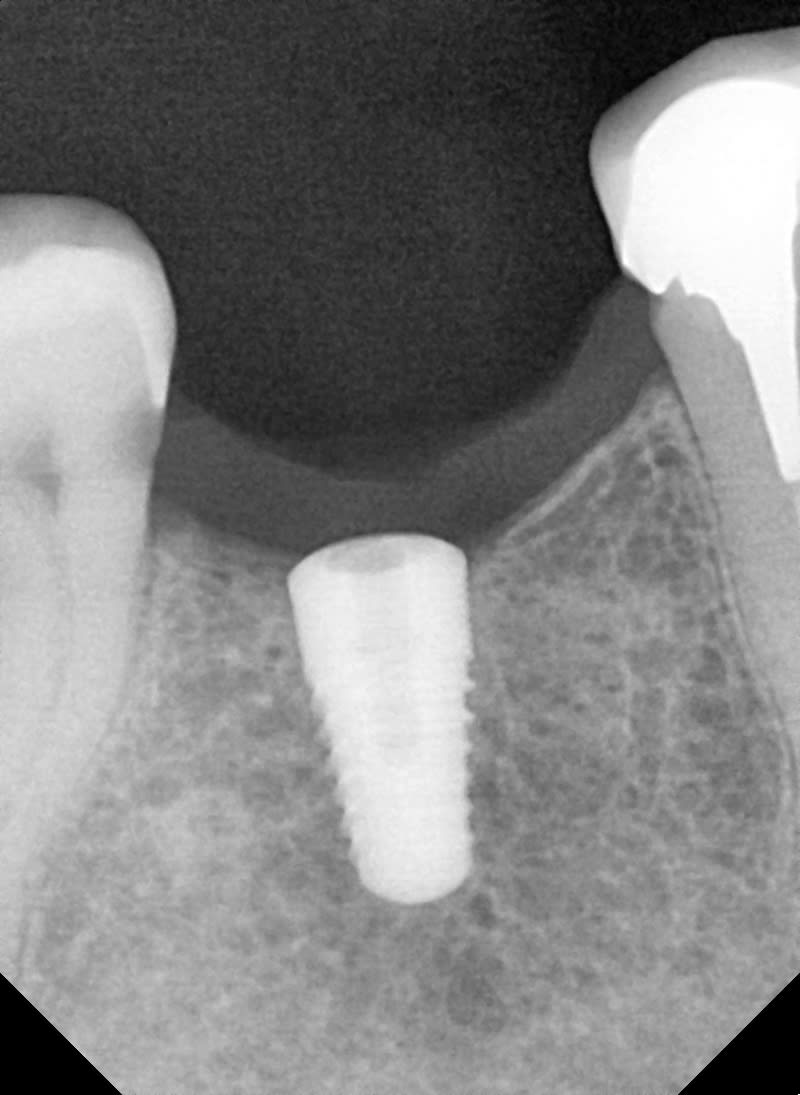

j aurai besoin de vos astuces pour retirer un hexagone de pilier personnalisé en titane qui est coincé dans l implant (etk).

la base du pilier s est déchirée et l hexagone est resté coincé dans l'implant au ras du col.

en gros c est pas terrible et je crains d'abimer le col de l implant

bon jai pu retirer la base avec ultrason newtron, l insert pour desceller les tenons et fraise metal, mon tourne gauche etait trop gros, celui que j ai est fait pour retirer les implants.

bien entendu j ai un peu abimé le rebord du col de l implant ce qui n est déjà pas top mais quand je remets un pilier de cica il y a des frottements terribles lors du vissage.

j ai l'impression que le pas de vis est compromis, apres une heure d effort je suis un peu déçu